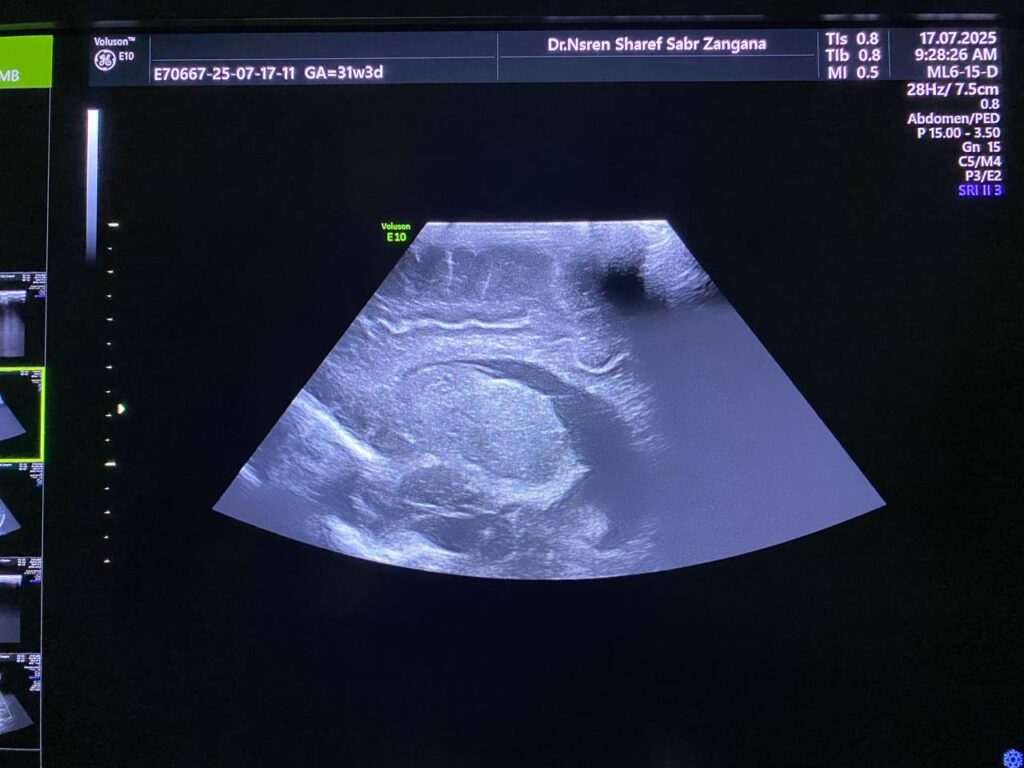

Associated with presence of of heterogenous mass 10x6mm , extruded from the brain tissue in the occipital region , mostly encephalocele